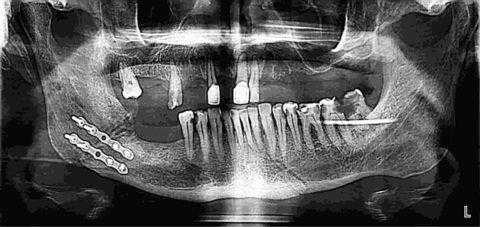

Установление накостных мини-пластин их металла

Показанием к такому виду хирургического вмешательства служат практически все виды переломов челюсти, кроме оскольчатых повреждений кости. Существенным преимуществом фиксации накостных пластин является необходимость доступа к костной ткани только с одной стороны.

Остеосинтез верхней челюсти таким методом заключается в наложении и прикручивании мини-пластины на совмещенные края переломанной кости.

В настоящее время большинство подобных оперативных вмешательств осуществляется внутриротовым способом, что исключает необходимость разреза кожного покрова.

Ход операции

Нижняя челюсть. Процедура выполняется под местной анестезией. Выполняют рассечение слизистой и надрез костной ткани позади коренных зубных элементов. Костную ткань распиливают, раздвигают и фиксируют при помощи пластин в требуемом положении.

В некоторых случаях проводится двухчелюстная остеотомия с целью исправления прикуса обеих челюстей. В среднем длительность процедуры занимает от 1 до 5 часов. Проводится хирургическое вмешательство в стационаре. Рассмотрев проведение остеотомии челюсти до и после, вы сможете оценить результат, настроить себя на проведение соответствующей процедуры.

Последствия и восстановление после остеотомии нижней и верхней челюсти

После процедуры начинается период реабилитации. Могут наблюдаться отеки, синяки, онемение, поэтому на этапе восстановления после остеотомии рекомендуется регулярно посещать специалиста. Фиксирующие элементы извлекают по прошествии 1-2 месяцев. Для лучшего результата могут быть установлены несъемные ретенционные конструкции. По завершении процесса реабилитации пациент начнет ощущать улучшение прикуса, наблюдать лицевую эстетику, что значительно повысит качество его жизни.